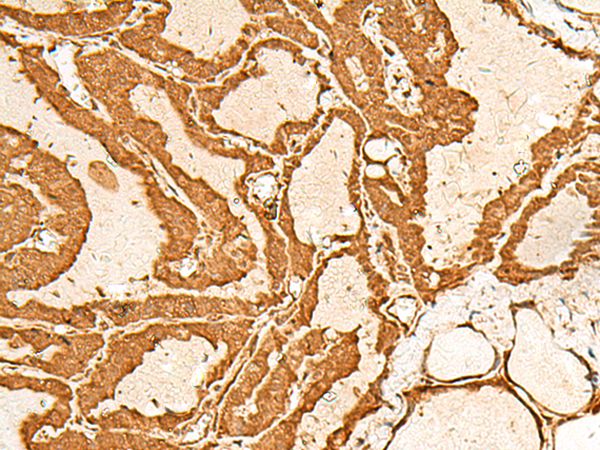

| IHC | 1/40-1/200 | Human,Mouse,Rat |

CHP1 antibodies are widely used in research to detect endogenous CHP1 expression, subcellular localization (e.g., cytoplasmic or membrane-associated), and interactions with NHE1 or other partners via techniques like Western blot, immunofluorescence, or co-immunoprecipitation. These tools have advanced understanding of CHP1's pathophysiological roles and its potential as a therapeutic target. Dysregulation of CHP1 has also been associated with neurological disorders, including Alzheimer’s disease, emphasizing its broad biological relevance.